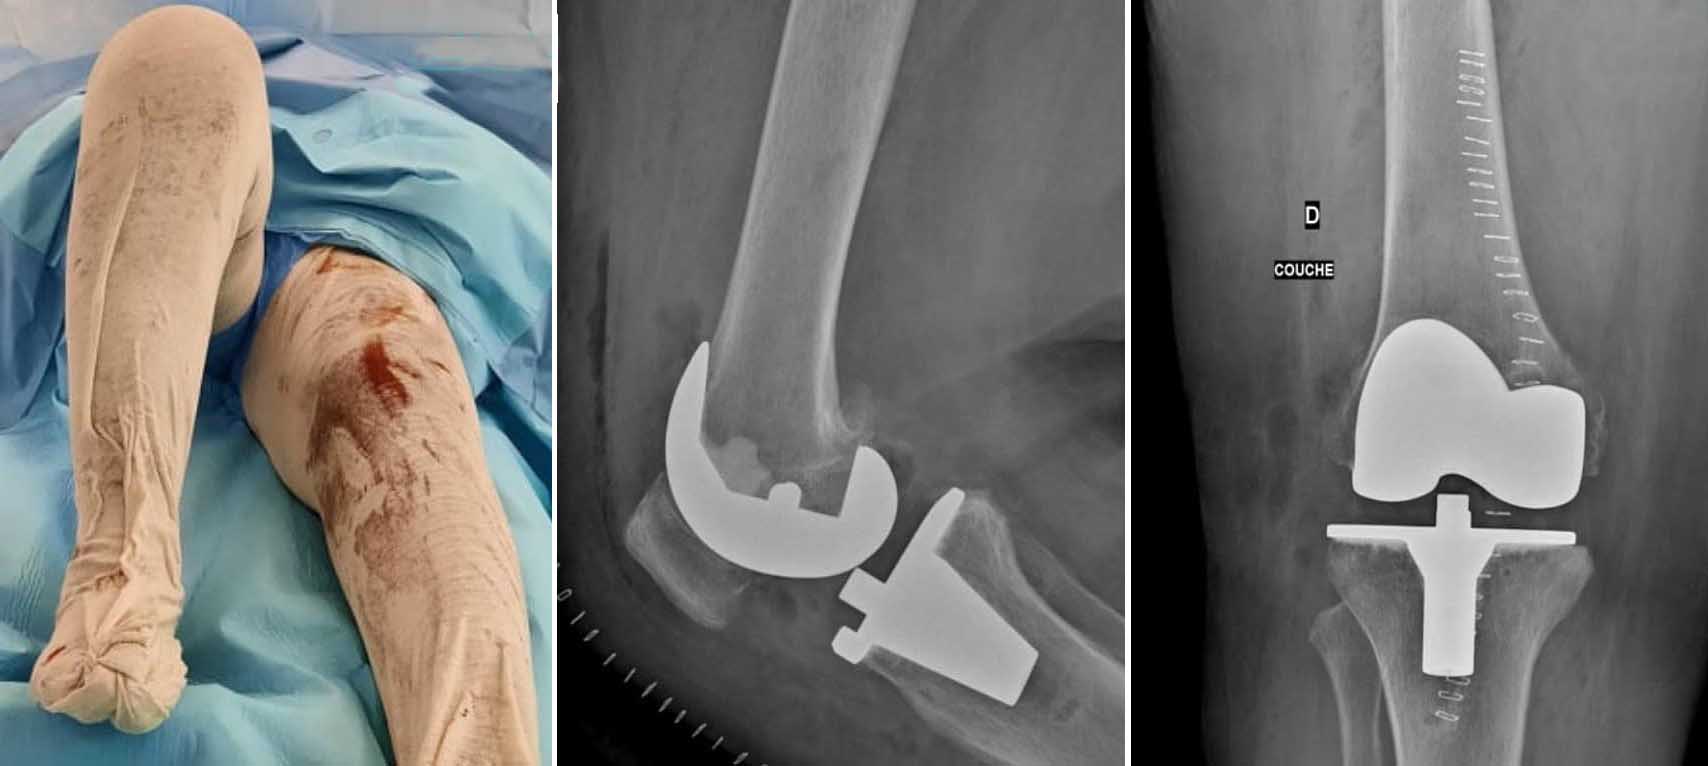

تمكن الفريق الطبي لمصحة ابن خلدون، مؤخراً من إجراء عملية تغيير لمفصل الركبتين في نفس الوقت وذلك لأول مرة في صفاقس، وقد تمكنت المريضة من المشي بصفة جيدة بعد أيام قليلة من العملية.

تهدف عملية استبدال مفصل الركبة إلى علاج تآكل الغضروف في مفصل الركبة، الذي يحدث غالبًا نتيجة لالتهاب المفاصل المزمن (Arthritis)، وتعتمد العملية على استبدال المفصل المصاب بمفصل آخر اصطناعي.